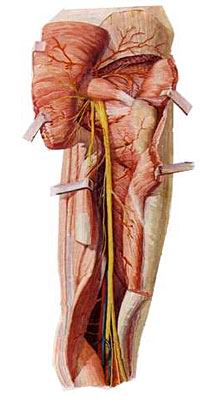

5.骶丛

(3)坐骨神经

坐骨神经是全身最大的神经。于梨状肌下缘出骨盆,行于臀大肌深面,经坐骨结节与大转子连线的中点,下行至腘窝,分为胫神经和腓总神经。坐骨神经本干布于髋关节和股肌后群。

1)胫神经

沿腘窝中线,经小腿后群肌深浅两层间下降,于内踝后方至足底分为足底内侧神经和足底外侧神经。

胫神经肌支支配小腿后群肌、足底肌。皮支布于膝关节、小腿后面皮肤、足底皮肤。胫神经损伤后表现为足“勾状外翻”。

2)腓总神经

沿腘窝上外侧缘向外,绕腓骨胫,分为腓浅、腓深神经。腓浅神经肌支支配小腿外侧群肌,腓深神经肌支支配小腿前群肌。腓总神经损伤后表现为足下垂伴内翻(即“马蹄内翻”)。